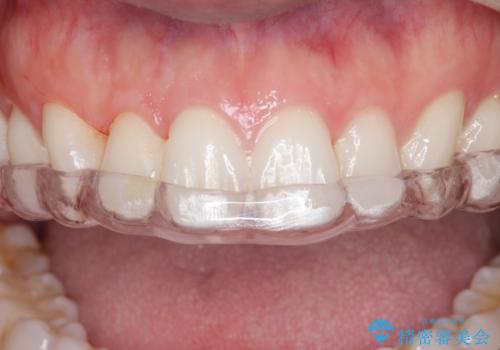

保険のナイトガードよりも穴が空きにくいナイトガードのご案内をしてフラットタイプナイトガード(自費でのご案内)

を作製することになりました。

ナイトガードを使用することによって歯がすり減る(寝ている時の歯ぎしりなど)事を防いでくれます。

保険のナイトガードよりも厚くて硬いので壊れたり割れたりする心配がありません。

またナイトガードを装着して全体的に噛む力が均等になるように調整を行います。